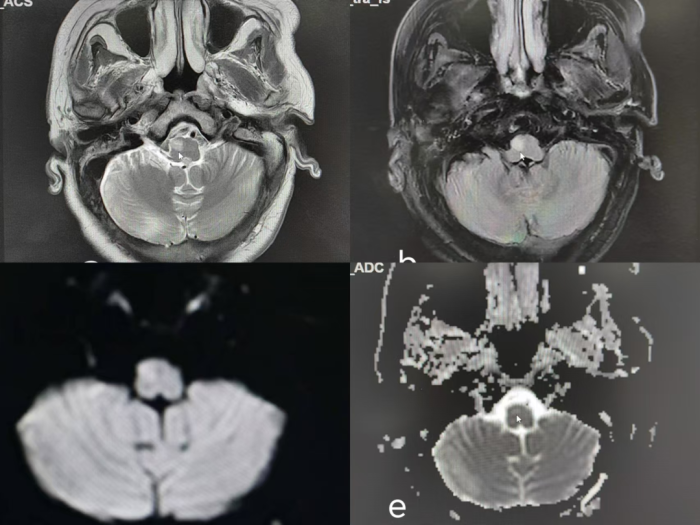

6月7日,患者头颅磁共振显示,其可见右侧中脑及脑桥T2WI及FLAIR中心高信号,周围低信号;右侧延髓T2WI高信号、FLAIR稍高信号

8月1日,患者复查头颅磁共振结果显示,右侧延髓T2WI、FLAIR、DWI呈高信号,ADC呈稍高信号

8月1日,患者复查头颅磁共振结果显示,右侧脑桥T2WI及FLAIR中心高信号,周围低信号